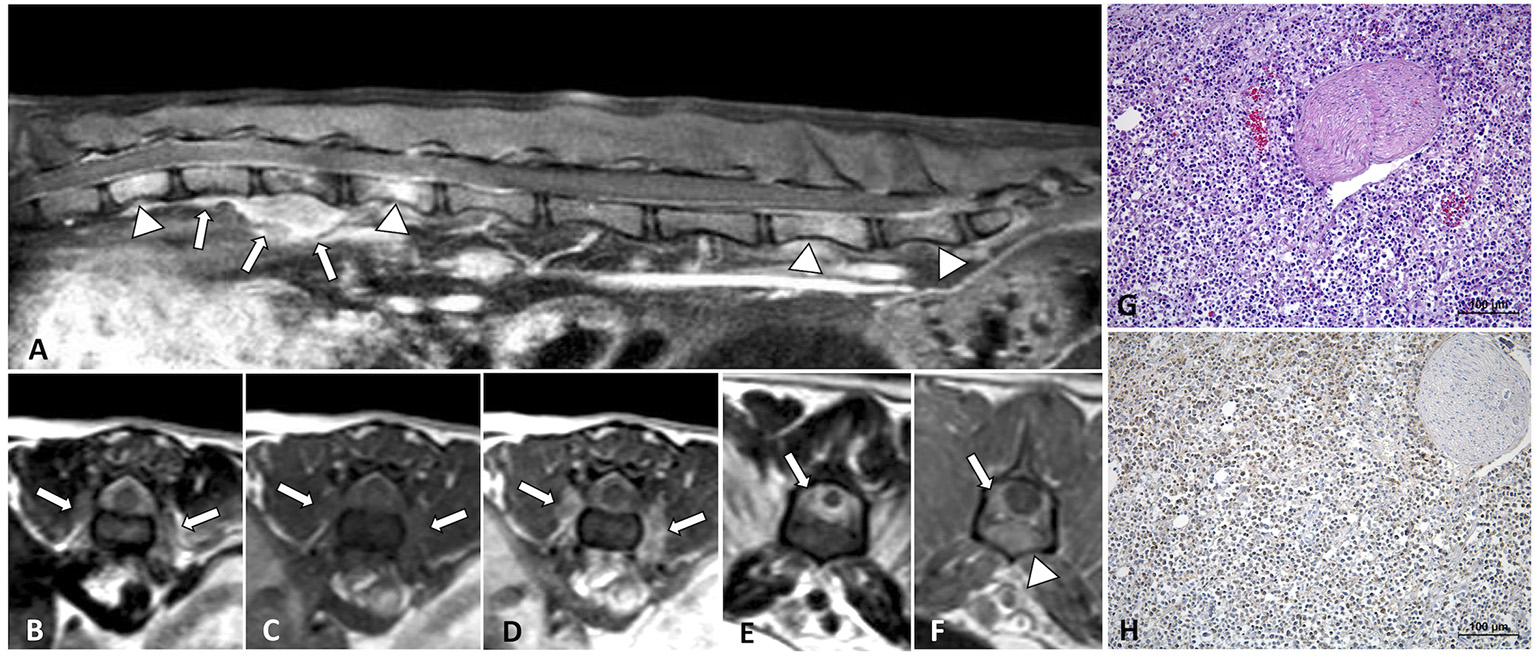

A paravertebral mass with vertebral canal invasion along nerve roots was found in 4/27 (14.8%) cases, localized at T2-T4 vertebrae, T5-T7, T8-T9, and T6-T12 vertebrae, respectively. In 1/27 (3.7%) case a paravertebral mass with vertebral canal invasion along nerve roots in T12-L3 vertebrae and a separate epidural lesion in L5-S1 vertebrae were depicted (Figure 4).

Figure 4

MRI of an 8-year-old domestic short-haired paraplegic cat diagnosed with multicentric small-intermediate T-cell lymphoma. Sagittal plane T1W post-contrast SPIR of the caudal thoracic and lumbar vertebral column (A) shows a paravertebral mass ventral to the L1 vertebra and extending cranially to T12 and T13 vertebrae (arrows) and irregular hyperintensity on the bone marrow of several vertebral bodies (arrowheads). Transverse planes at the level of T13-L1 intervertebral space (B–D) show an extension of the paravertebral mass through the intervertebral foramina (arrows) and to the epidural space circumferential to the spinal cord. The lesion is hyperintense on T2W (B), isointense on T1W (C), and enhances with a mild heterogeneous pattern on post-contrast T1W (D) images. Transverse planes T2W (E) and post-contrast T1W (F) at the level of the L6 vertebra, show an epidural diffuse infiltrate (arrows) with similar signal features. Hyperintensity of the vertebral body with cortical sparing is also depicted (arrowhead in F). On histopathology image, HE (G) neoplastic lymphoid cells are surrounding a nerve root, on IHC (H) T-lymphocytes, CD3-immune positive cells, predominate in the tumor.